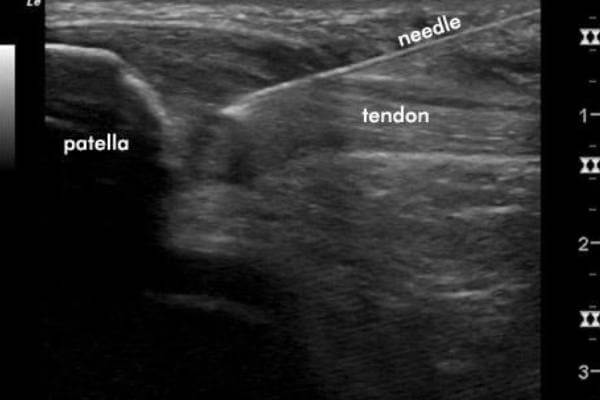

Tendon Fenestration involves passing a needle through the abnormal tendon multiple times (20-25 times) to change a chronic degenerative process into an acute condition that is more likely to heal.

In the Foot and Ankle this is beneficial for Achilles Tendinopathy and Plantar fasciitis. It is very important that the region is numb for this procedure with the use of local anaesthesia. Ultrasound guidance ensures that the needle is passing through the areas of tendon degeneration.

The needle is passed through the plantar fascia around 20 – 25 times to change the chronic degeneration of the tendon into a more active acute response.